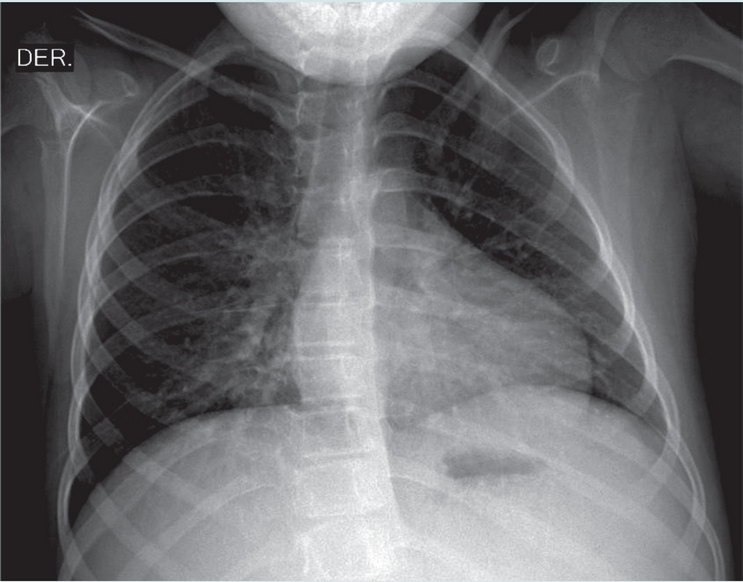

En los exámenes de laboratorio destacó bicitopenia (leucopenia con neutropenia y trombocitipenia). La radiografía de tórax mostró cardiomegalia, rectificación del cono de expulsión de la arteria pulmonar e infiltrado intersticial reticulonodular bilateral, con patrón en vidrio despulido basal derecho (Figura 2). Una semana después presentó insuficiencia respiratoria aguda para la cual requirió de ventilación mecánica por 11 días, con mejoría clínica con manejo intensivo. Se valoró tomografía computada de alta resolución (TCAR) pulmonar en la que se observó patrón en mosaico bilateral, con áreas de ocupación alveolar e importante aumento del calibre de las estructuras vasculares (Figura 3).